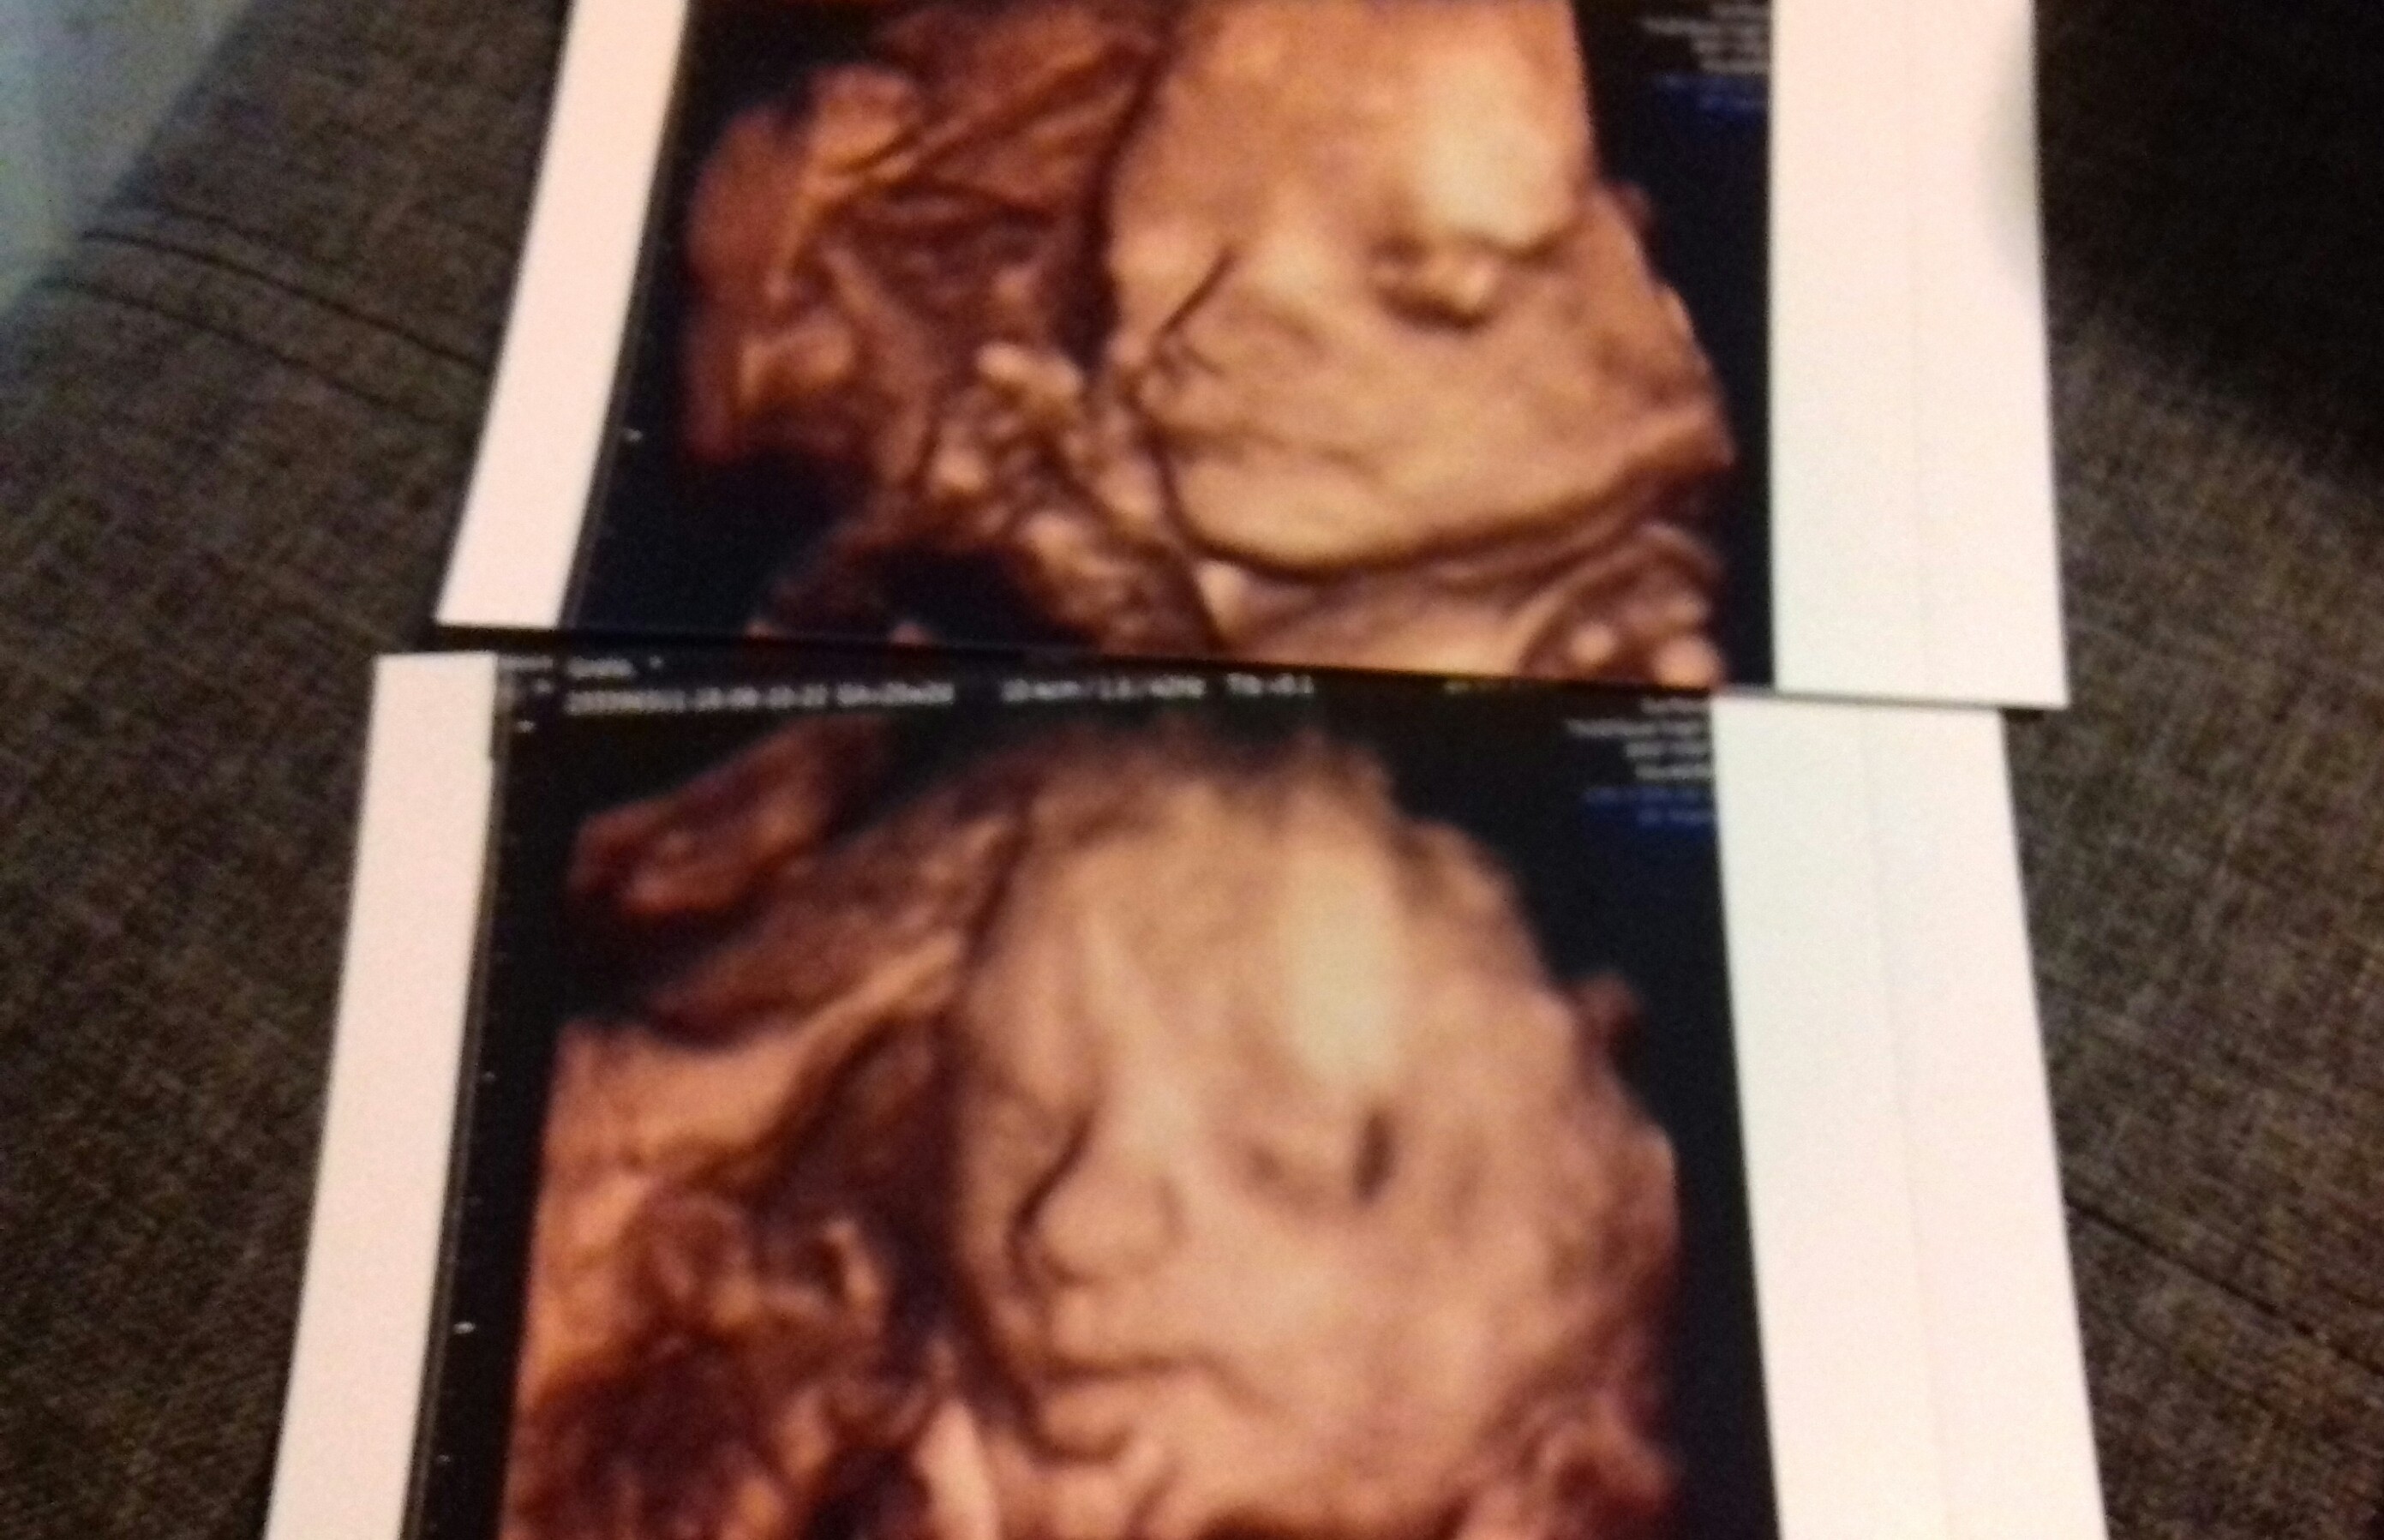

Dla pocieszenia -Nasza Księżniczka :)

Załączniki

• 20180810_215135-1.jpg

20180810_215135-1.jpg

727,5 KB · Wyświetleń: 120